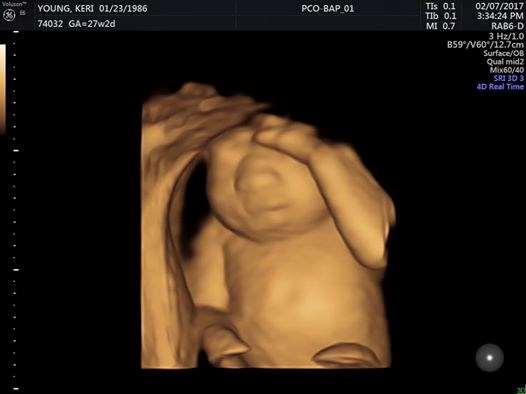

Ройс и Кери Янг се подготвят да посрещнат на бял свят своето второ дете, когато през 19-ата седмица от бременността разбират, че нероденото им момиченце страда от аненцефалия - рядко и неизлечимо заболяване, което пречи на нормалното развитие на мозъка и костите на черепа.

Междувременно бременността на Кери протича нормално.

"В момента тя е здрава, усещам как рита, как се движи. Сега не е време да тъжа, ще имам цял живот за това, сега Ева е жива", споделя Кери Янг.

Ева ще се появи в живота на Ройс и Кери Янг, макар и за малко, след малко повече от месец - на 7 май.